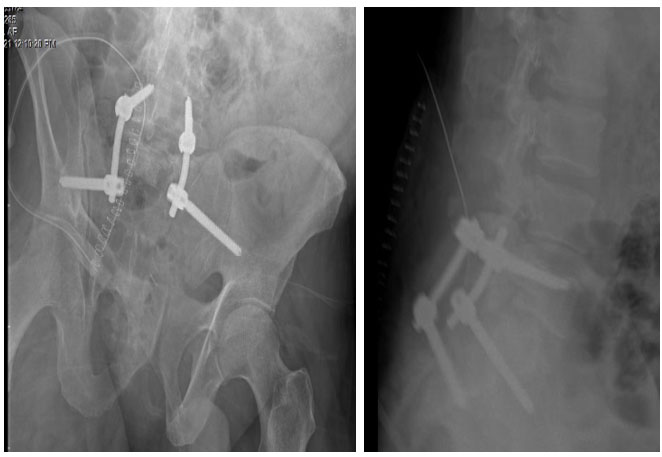

Ameliyat sonrası: Lumbopelvik fikasyon radyolojik görüntüsü